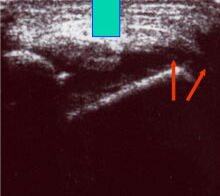

Ruptur Lig. fibulotalare anterius

Lagerung: Rückenlage, OSG in Plantarflexion.

Schnittebene: LS über Lig. talofibulare anterius.

Referenzstrukturen: Fibulakante und Talushals.

Befunde: Das Lig. talofibulare ant., verläuft (mit häufigen Anlagevarianten) beim Gesunden als meist dreieckige oder parallele echogene Struktur von der Fibula bis zur Spitze des im Schnitt pyramidenähnlichen Talus. Darunter ist ggf. Gelenkknorpel erkennbar (Abb. 15). Beim Erwachsenen reißt das Band meist distal ab und schlägt sich zum Talus hin ein (Abb. 16). Bei Kindern reißt das Band meist mit einer osteochondralen Schuppe fibular ab (Abb. 17). Zwischen Band und Knochen drängt oft echoarmes Hämatom nach außen, das im Dekompressionstest deutlicher darstellbar wird (Abb. 18). In derselben Untersuchungsposition kann die Stabilität schnell und weitgehend schmerzfrei überprüft werden (s. u.).